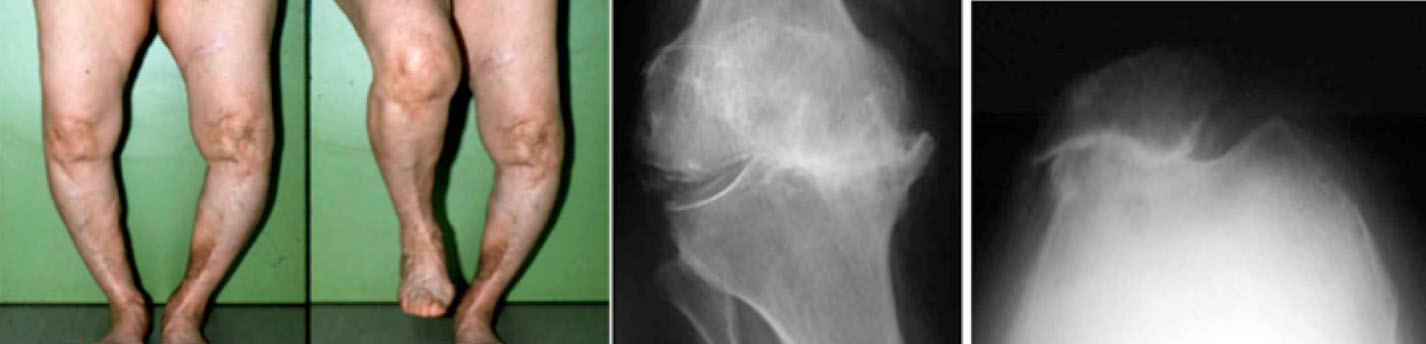

- L’arthrose fémoro-patellaire survient sur une instabilité rotulienne ancienne ou un déséquilibre ancien longtemps bien supporté. La majorité de ces patients présentent une usure du compartiment externe et une subluxation externe de leur rotule. Cette arthrose fémoro-patellaire isolée est très longtemps bien supportée et le traitement est médical et kinésithérapique (étirements, renforcement des ischio-jambiers,

physiothérapie). Le traitement chirurgical est rare car les résultats sont très inconstants (patellectomie partielle externe, régularisation d’ostéophytes, transposition-avancement de la tubérosité tibiale). Certaines techniques sont mêmes quasi abandonnées (spongialisation de rotule). Enfin, dans certains cas extrêmes, on pose une prothèse isolée de la rotule si le reste du genou est bon.